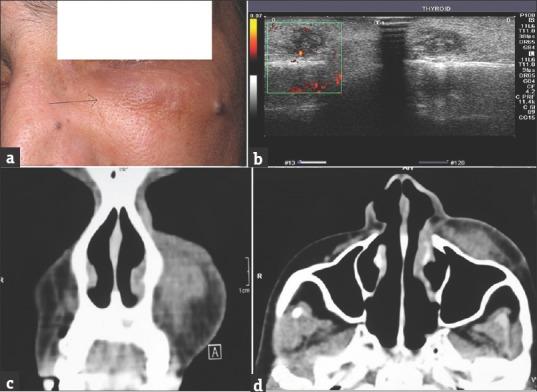

Dirofilariasis is a parasitic infection transmitted by mosquitoes from domestic and wild animals. Humans accidentally get infected and can present with a lung nodule, subcutaneous mass or an ocular lesion which will be either subconjunctival or periorbital. Proper microbiological and histopathological examinations aid in proper diagnosis. Herein, we present a case report of a 64-year-old female patient from Kerala with an infraorbital mass diagnosed as dirofilariasis.

丝虫病是一种由蚊子从家畜和野生动物传播的寄生虫感染。人类意外感染后可能会出现肺结节、皮下肿块或眼部病变,后者表现为结膜下或眶周病变。适当的微生物学和组织病理学检查有助于做出正确诊断。在此,我们报告一例来自喀拉拉邦的64岁女性患者,其眶下肿块被诊断为丝虫病。